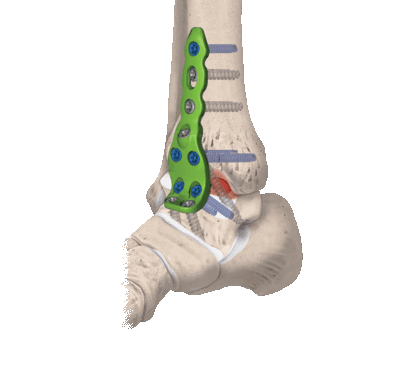

- Внутрисуставный. В процессе хирургии выполняется вскрытие капсулы сустава с последующим удалением поврежденного гиалинового хряща с поверхностей костных элементов. После репозиции костей в выгодном положении выполняется их фиксация металлическими приспособлениями.

- Внесуставной. Фиксирование костей сочленения только при помощи укладки костного трансплантата, при этом хрящевые покровы резекции не подлежат.

- Комбинированный. Эта техника подразумевает сочетание в одном хирургическом процессе двух способов: внутрисуставного и внесуставного. Так, хрящевые структуры с сустава полностью счищаются, внедряется аутотрансплантат, который фиксируют специальными металлическими пластинами.

- Дальше стопа выводится из порочного положения. Большеберцовый элемент и таранный компонент плотно сопоставляют друг с другом в удобной с точки зрения физиологии позиции. Достигнутая позиция скрепляется металлической конструкцией необходимого типа.

- Используемые операционные ходы на завершающем этапе закрывают при помощи послойного ушивания мягких тканей с оставлением дренажа.